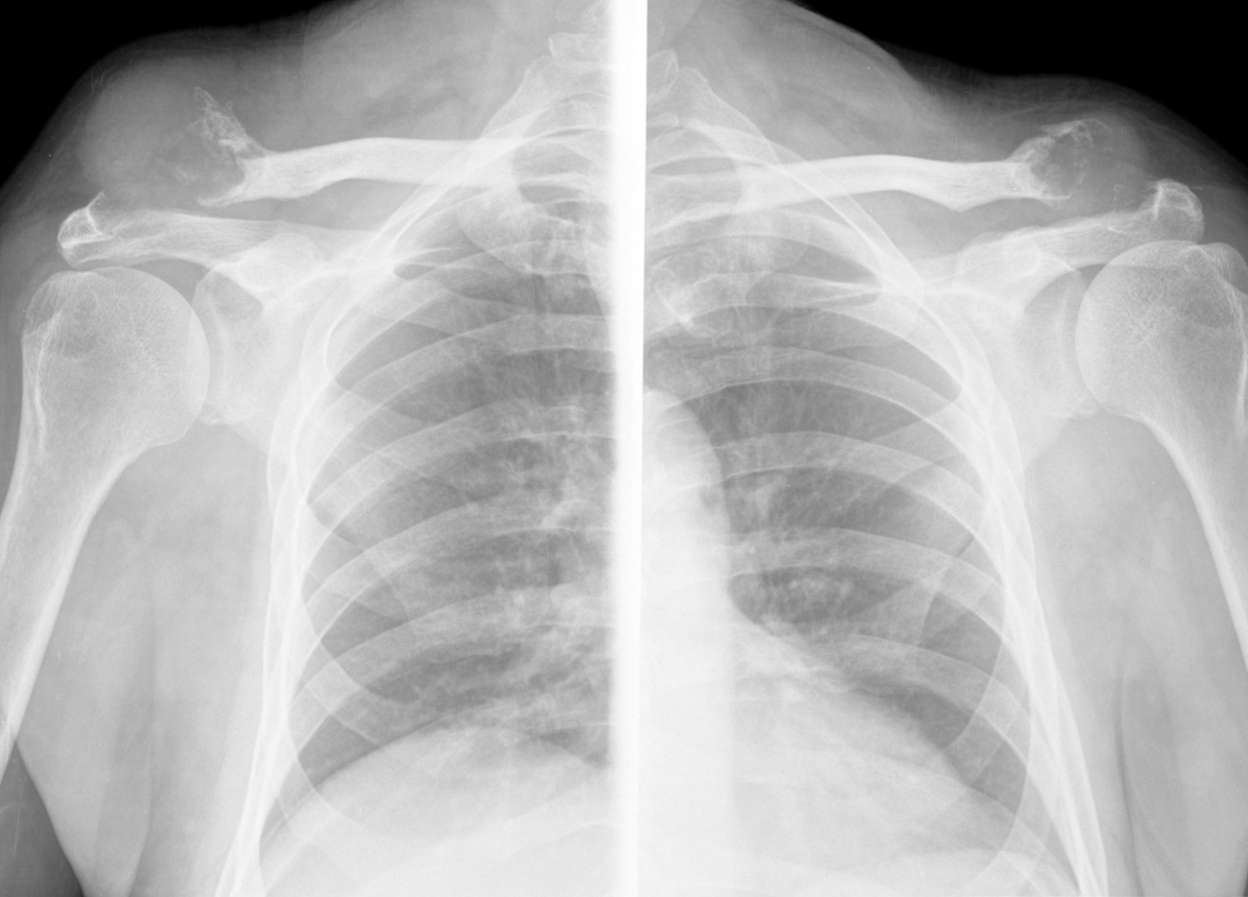

Вводные данные: 70 лет, рак мочевого пузыря (подтвержден), мтс в кости (по КТ). В анамнезе: ИБС, гипертония, подагра, сахарный диабет. Направлен на химиотерапию.

При поступлении, выполнена рентгенография легких. Выявлены изменения в ключицах.

Что думаете?

О метастазах в ключицы впечатление, конечно, не складывается. Необходимо думать о системных процессах. Возможны с большими натяжками и подагрическая, и диабетическая артропатия. Но, на мой взгляд, лабораторно надо исключить гиперпаратиреоидную ОД.

А не обращает внимание в каких отделах ребер и позвонков изменения?